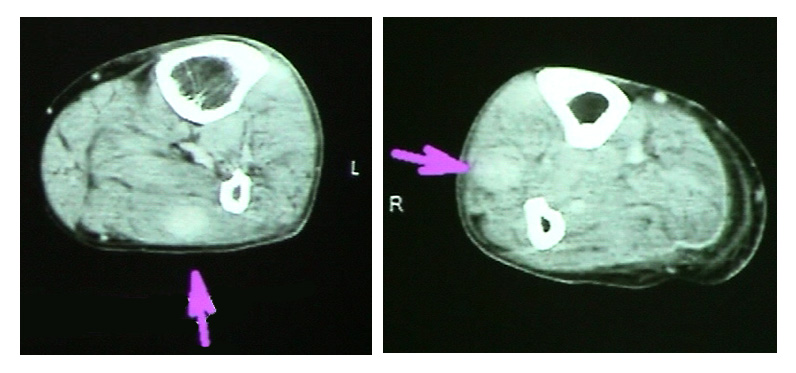

転院後AV療法(AraC+VP-16)開始。感染症に対して抗生剤および免疫グロブリンの投与が行われる。その後臍帯血移植施行し好中球生着が確認された。移植4週後から右下腿後面アキレス腱付近に筋肉痛症状が出現する。移植5週後, 発熱と右頸部に圧痛を伴う3cmほどの腫瘤を触知。造影CTでは頸部には明らかな病変は確認されなかった。両側下腿筋肉内には斑状濃染域が見られた。後日MRIで同様の所見が認められた。